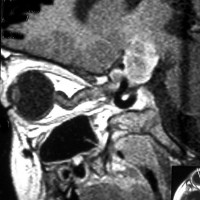

生後7カ月の幼児です。目が揺れるようになり(振り子様眼振)眼科を受診して腫瘍が発見されました。小児脳腫瘍の治療ができる病院へと紹介されました。

1ヶ月後にまたMRI検査がされました。乳児ですから検査にも麻酔が必要です。腫瘍は明らかに大きくなっています。左視神経から視索の腫瘍化が著しいので右側だけかすかに視力が残っているかもしれません。視力は明かりがわかる程度(明暗弁)と評価されました。

主治医の先生からこの赤ちゃんの両親に手術が提案されました。理由は,「とってみなければどんな腫瘍かわからない,病理診断ができないと制癌剤(化学療法)が選択できない」というものです。

こんなことを書くのは悪いことかもしれませんが,まったく馬鹿げた提案です。この画像はどこをどう見ても視路から発生した毛様粘液性星細胞腫です。画像はpathognomonic(日本語で火を見るよりも明らか)です。この小さな子に,全身麻酔をして開頭手術で生検病理診断すれば,それだけで3週間は化学療法の開始が遅れます。その間に明かりも見えなくなってしまう(完全失明する)可能性が高いでしょう。2021年時点でも,開頭手術による生検術は行われていますが,こんな重病の小さな子どもの頭を無用に開くなど,私にはもう理解不能です。

この様な増殖力が早い毛様粘液性星細胞腫は,髄液播種(脳脊髄に広範囲に転移)することがあります。手術で細胞を散らせば致命的な播種を誘発する可能性さえあります。